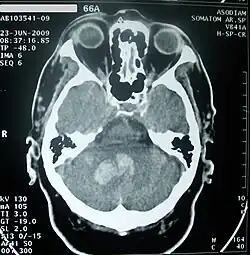

Imagerie cérébrale

Elle permet de voir l'accident vasculaire, de le dater en partie, d'en connaître le mécanisme, d'éliminer d'autres maladies pouvant être responsable de l'accident déficitaire.

Le scanner crânien est fait, sauf contre-indication, avec injection d'un produit de contraste iodé. Si l'accident est ischémique, il permet de visualiser la topographie, l'étendue et le nombre de lésions. S'il est hémorragique, il en fait le diagnostic.

L'imagerie par résonance magnétique crânienne, faite également après injection d'un produit de contraste, donne le même type de renseignements mais est plus sensible si l'accident est très récent. Elle peut être complétée dans la même séance par une angio-IRM permettant de visualiser les grands axes vasculaires extra et intracrâniens.